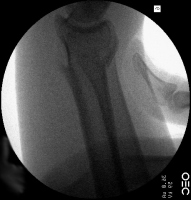

Case 5

Young man sustained bilateral metacarpal fractures.

The left hand injury included a small metacarpal base

comminuted fracture subluxation. |

| Percutaneous

fixation. |

| Thermoplastic

stabilization. |

| The right hand sustained a small metacarpal neck fracture with palmar angulation. |

| Reduction and

| Pin

| Pins were

removed at four weeks. Appearance at eight weeks

after surgery. |